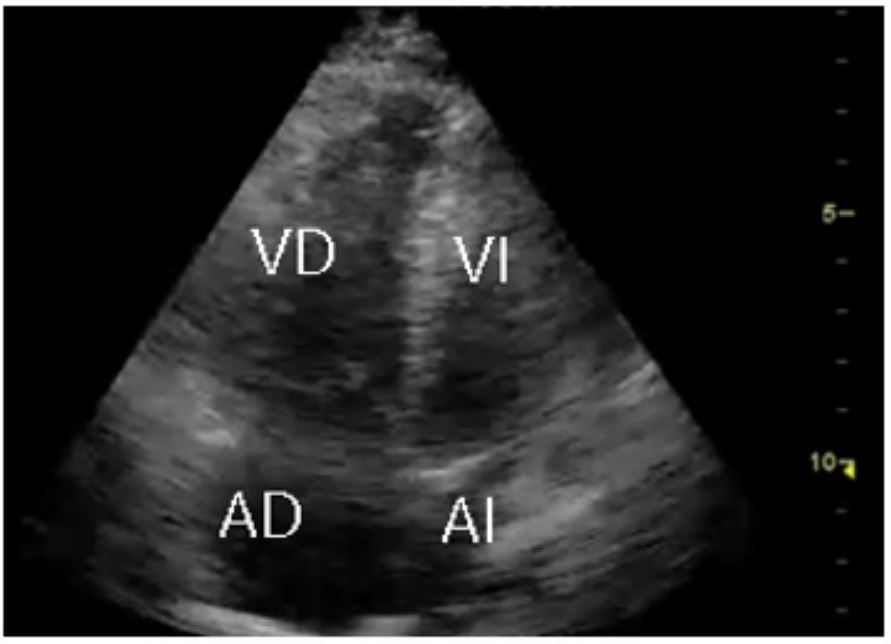

En las salas de reanimación, la paciente tuvo bradicardia extrema súbita y, posterior a ello, paro cardiorrespiratorio, con ritmo de actividad eléctrica sin pulso (AEP); por ello, se le hizo reanimación cardiopulmonar según el protocolo de la Asociación Americana del Corazón y, así, se obtuvo retorno de la circulación espontánea (ROSC). Posterior a ello se indicó el inicio de soporte inotrópico y vasopresor con dobutamina y noradrenalina. Además, con el protocolo CAUSE se trató de enfocar la causa específica del paro cardiorrespiratorio con ritmo no desfibrilable, ya que inicialmente se pensó que su causa era por un posible síndrome coronario agudo, debido a la presencia del bloqueo completo de la rama izquierda. Se encontraron signos indirectos de TEP, en planos paraesternal largo y corto (figura 2a y 2b) y apical de cuatro cámaras (figura 3). Se procedió a la toma de una angiotomografía computarizada de tórax, que confirmó el diagnóstico de TEP agudo con signos de sobrecarga derecha (figura 4); por ello, se procedió a realizar una trombólisis con 50 mg de alteplasa. A pesar de los manejos instaurados, la paciente fallece después de recibir 20 minutos plenos de reanimación cardiopulmonar.

VD: ventrículo derecho; VI: ventrículo izquierdo; AD: aurícula derecha; AI: aurícula izquierda.

Para evaluar la presencia de TEP, el examinador debe evaluar los signos de disfunción ventricular derecha, como un VD dilatado y un VI relativamente pequeño (8). El ecocardiograma transtorácico tiene una sensibilidad, especificidad, valor predictivo positivo, valor predictivo negativo y precisión para el diagnóstico de TEP del 75 %, del 89 %, del 92 %, del 67 % y del 80 %, respectivamente (9).

La utilidad del uso del ultrasonido radica en la identificación de datos indirectos de TEP y no del émbolo propiamente dicho (raramente visualizable) (12). Los datos que sugieren sobrecarga del VD son el diámetro ventricular >40 milímetros (mm), disfunción sistólica de moderada a severa y gradiente sistólico tricúspideo mayor a 50 mm de mercurio. Los signos más importantes para el diagnóstico diferencial, aun en presencia de enfermedad cardiorrespiratoria previa y como pronóstico, son el signo de McConell y el signo de 60/60. El signo de McConnell, descrito en 1996, consiste en una marcada alteración regional de la motilidad parietal del VD observada en vista apical cuatro cámaras con acinesia/hipocinesia de los segmentos medios y basales de la pared libre y relativa preservación de la región apical (13). El signo 60/60 es un tiempo de aceleración de la válvula tricúspide menor a 60 milisegundos en presencia de un gradiente sistólico tricúspideo mayor a 30 pero menor a 60 mm de mercurio (14). La coexistencia de un VD hipocinético agrandado con el signo de McConnell, junto con el signo 60/60, parece ser el criterio ecocardiográfico más útil para la disfunción del VD (13).